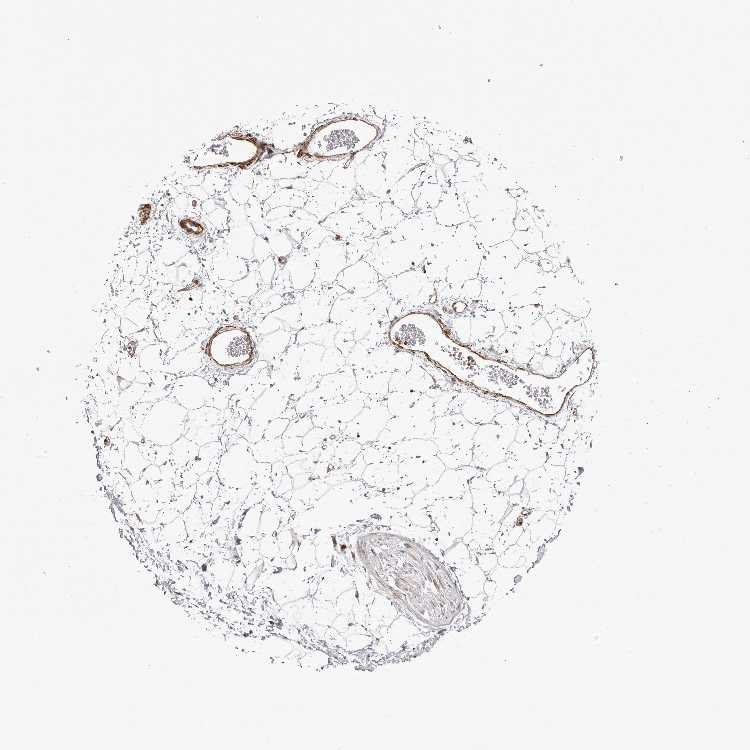

SOFT TISSUE 1 - Antibody stainingi

Antibody staining in the annotated cell types in the current human tissue is reported as not detected, low, medium, or high, based on conventional immunohistochemistry profiling in selected tissues. This score is based on the combination of the staining intensity and fraction of stained cells.

Each image is clickable and will lead to virtual microscopy that enables deeper exploration of all samples and also displays staining intensity scores, fraction scores and subcellular localization as well as patient and tissue information for each sample.

Antibody HPA023636Antibody HPA027962

Chondrocytes Low-

Fibroblasts Not detectedNot detected

Peripheral nerve -Low